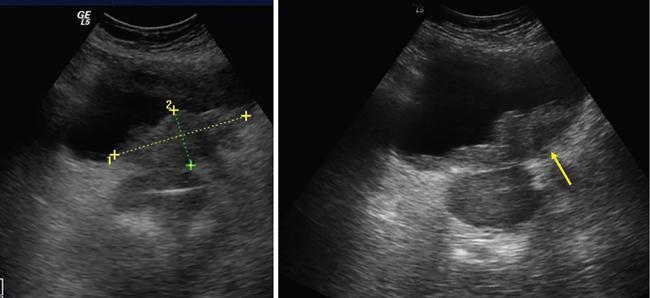

Complete or incomplete septae often seen (Fig. 11.4.1.2A).

Ovarian cysts are anechoic lesions noted on one side of pelvis (Fig. 11.4.1.2B). Normal ovarian stroma can be seen around the cysts in case of small cysts.

Colour Doppler shows vascularity in the septum (Fig. 11.4.1.2C).

Solid components more commonly seen (Fig. 11.4.1.2D).